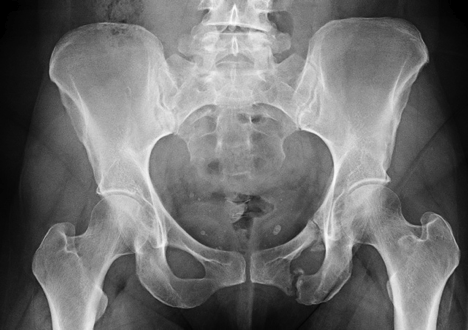

The fractures affected all four pubic rami (fig 1). This assumption of a stable injury in our case led to the patient being actively mobilised with early discharge home following. If fractures of the pubic rami are grossly displaced and unstable, the indications are stronger.

On physical examination, pain may be elicited on palpation directly over the pubic ramus. What we commonly call our hip bones are actually each three separate bones: The inferior end of the 'c' made by the lunate surface is broader and more blunt than the superior end. The left inferior and superior pubic ramus, and slightly. This is an edited version of the source image made for use in the anatomist ios and android app and shared here under the terms of the source image's share. Anteriorly following muscles originate from it Inferior pubic ramus, inferior ramus of pubis, ramus inferior ossis pubis. A stable fx of the pelvis is what. Fractures of the superior (in two places) and inferior pubic rami on the person's right, in a person who has had prior hip replacements. It blends with the inferior ramus of the ischium, and encloses the obturator foramen as a result and creates the pubic arch. Nonetheless, the above prior work all only focuses on diagnosing hip fractures and does not attempt to classify the more complex pelvic fractures (fractures in three pelvic bones: Fatique fracture is a fracture of normal bone which is subjected to repeated unaccustomed loading such as fractures of the inferior pubic ramus in new army recruits. The inferior pubic ramus goes downwards and laterally from the lower part of the body of pubis. This immobilization is often complemented by. A nondisplaced calcaneus fracture is a stable fracture where the broken ends of the bones meet up correctly and are aligned. An associated fracture of the inferior pubic ramus is present. On physical examination, pain may be elicited on palpation directly over the pubic ramus.